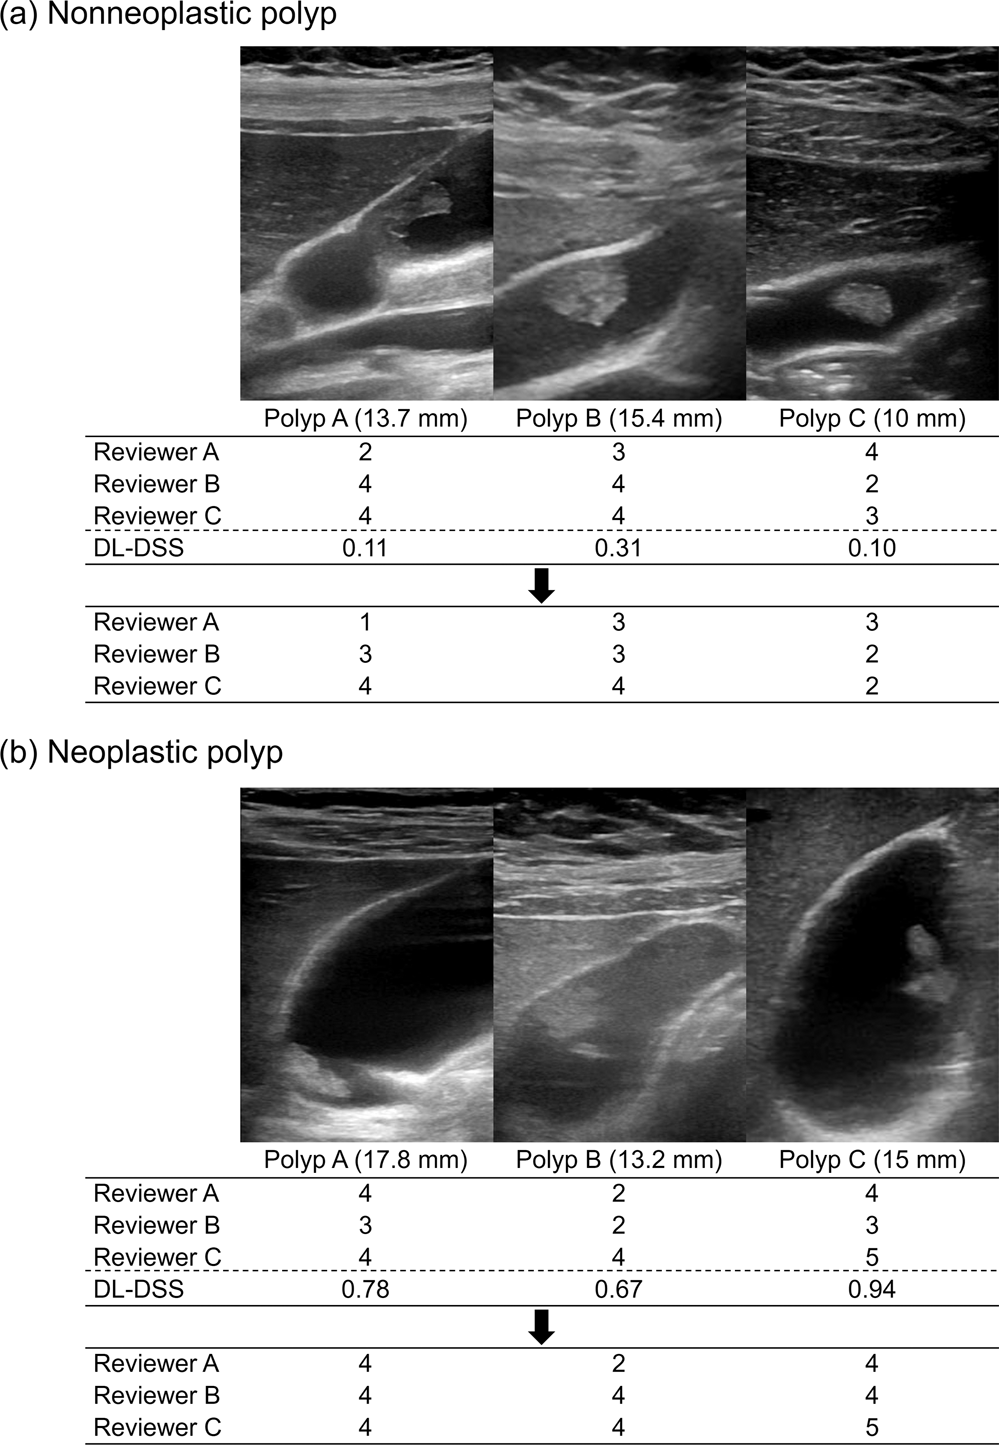

Figure 2

Example cases showing the effectiveness of DL-DSS aided diagnosis. (a) Three patients with a nonneoplastic polyp, measured over 10 mm size. Majority of the reviewers regarded these polyps as neoplastic polyp with confidence scale 3 or more. However, patient-level probability value was from 0.1 to 0.3 suggesting nonneoplastic polyp more likely. On the re-evaluation, some of the reviewers downgraded the score. (b) Three patients with a neoplastic polyp, measured from 13 to 18 mm size. Some of the reviewers classified these polyps as nonneoplastic polyp with confidence scale 3 or less. On the other hand, patient-level probability value was from 0.7 to 0.9, favoring neoplastic polyp. On the re-evaluation, some of the reviewers upgraded the score.